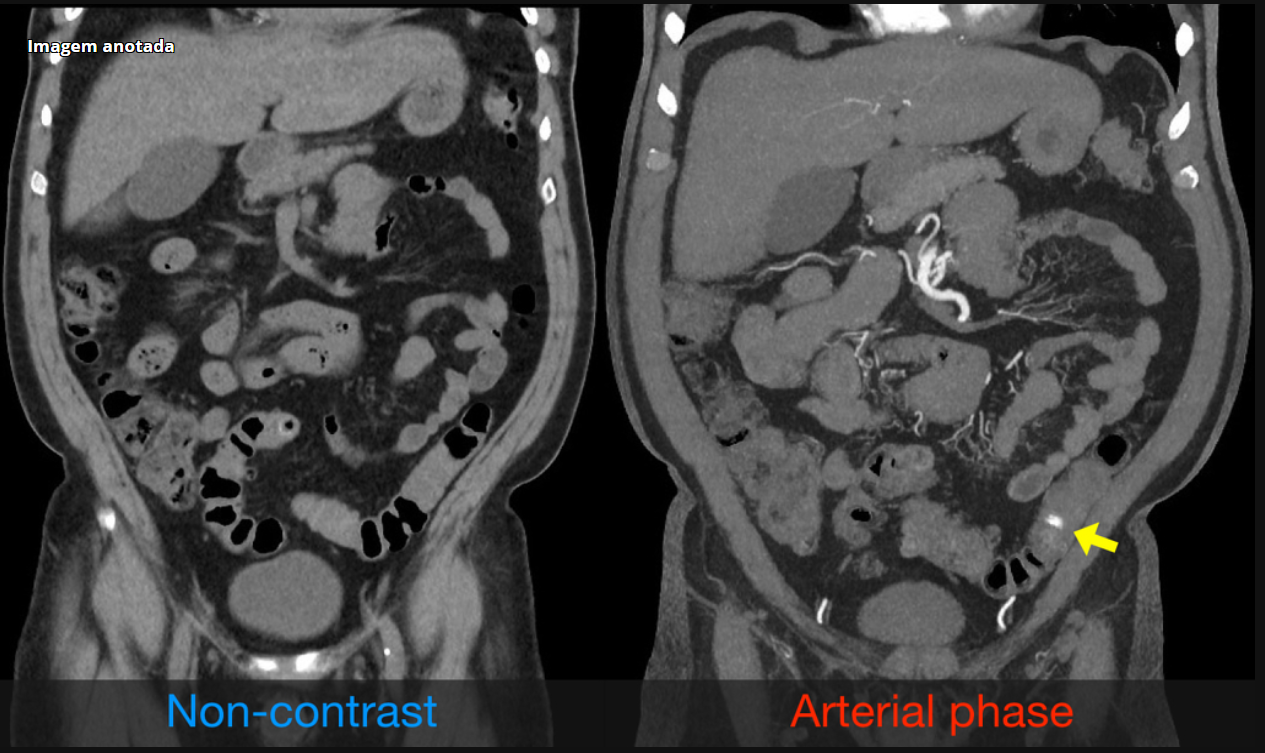

Sangramento gastrointestinal por angiodisplasia

É notado um extravasamento de contraste para o interior do lúmen do colon durante a fase arterial.

Não se observam sinais inflamatórios ou neoplásicos.